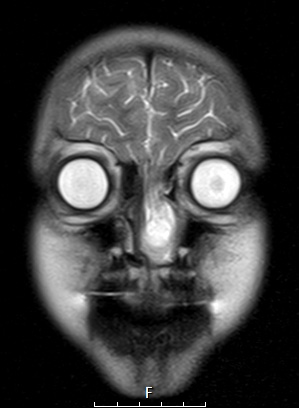

Washington University Experience | DEVELOPMENTAL MALFORMATIONS | Encephalocele - Nasal Glioma | 6A4 T2 Haste CORNoC (Case 6)

Direct connection of the intranasal brain tissue into the left nasal cavity as shown in T2 Haste scan.